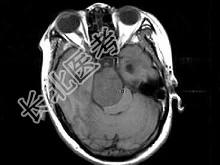

- 单项选择题女,32岁, 头痛、右侧肢体功能障碍约1年,声音嘶哑, 饮水呛咳,根据所提供图像, 最可能的诊断是 ( )

A、(斜坡)脑膜瘤

B、(斜坡)脊索瘤

C、(斜坡)神经鞘瘤

D、(斜坡)软骨瘤

E、(斜坡)海绵状血管瘤